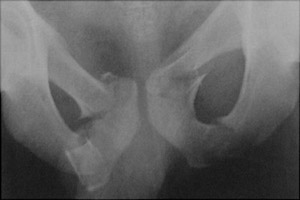

Bilateral superior and inferior rami fractures are known as a straddle injury. This was originally described in horseback riders and is the result of direct trauma. Urethral injury is a known complication.

- Click on the image for a larger versionAAP radiograph of the pelvis. This shows bilateral inferior and superior pubic rami fractures